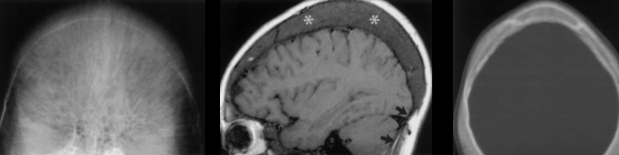

Cerveau

- AVCs ischémiques (200x risque)

- Troubles perfusionnels ++

- Sténoses vasculaires

- Territoires jonctionnels (Carotide++)

- Rarement Thrombo-emboliques

- Moya-Moyas

- Anévrismes

- Elargissement de la diploe (Aspect moucheté)